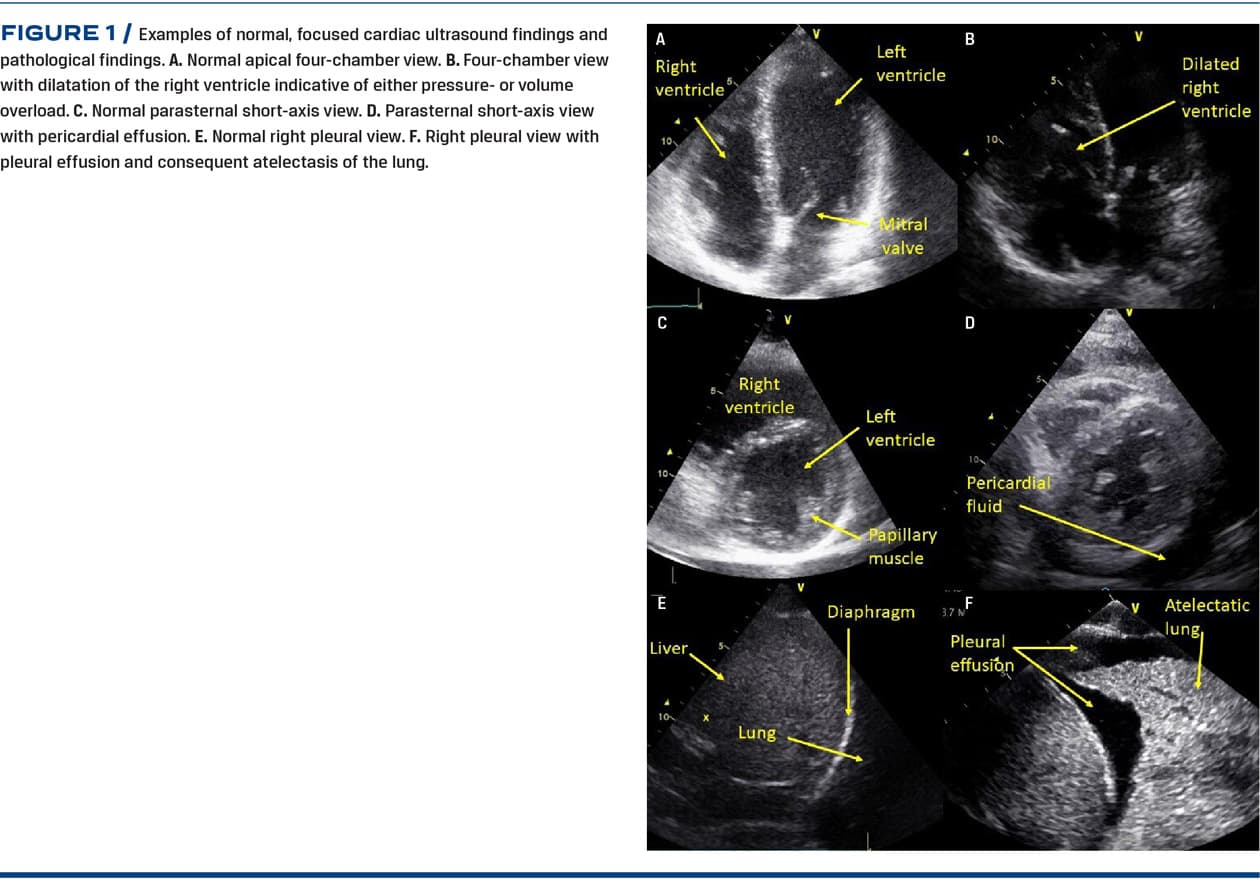

FOCUS follows the principle formulated in the focused assessed transthoracic echocardiography (FATE) protocol [8]. In short, FOCUS provides information on cardiac status and pleural effusion by the following views: Apical four-chamber view, apical five-chamber view, parasternal long-axis view, parasternal short-axis view, subcostal four-chamber and inferior vena cava view, and bilateral pleural views. See Figure 1 for examples of normal anatomy and common pathology. Two-dimensional grey-scale cine loops are stored from each view and the data extracted are fed into the web-based REDCap (Research Electronic Data Capture) data capture tool [17]. The data extracted are based on visual evaluation of cine loops including eye-balling, simple calibration and M-mode. Activation of Doppler modalities are not allowed. The data from each view are synthesised to automatically generate a FOCUS report that is made available to the anaesthesiologist ultimately responsible for providing anaesthesia to the patient. Please see Figure 2 for a FOCUS report example. The report contains information on:

• Left ventricle: systolic function, myocardial dyskinesia, size, diastolic function and myocardial thickness

• Right ventricle: systolic function, size, signs of acute/chronic pressure overload

• Valves: aortic and mitral valve pathology

• Volume status, pericardial effusion, pleural effusion and other pathology.